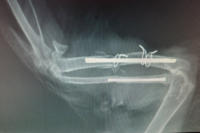

Die Röntgenstrahlen durchdringen den Körper und ermöglichen so innerhalb weniger Minuten ein Bild von den Knochen und den inneren Organen unserer Haustiere zu bekommen. Das Röntgenbild leistet unter anderem bei Lahmheiten und der Diagnose von Krankheiten des Herzens, der Verdauungsorgane und der Harnwege wertvolle Dienste. In der Ordination steht ein modernes Röntgengerät mit digitaler Entwicklung zur Verfügung, Vorteile sind die hervorragende Bildqualität für genaue Diagnostik, Versand der Bilder per e-mail (an den Besitzer) und Archivierung am Computer.